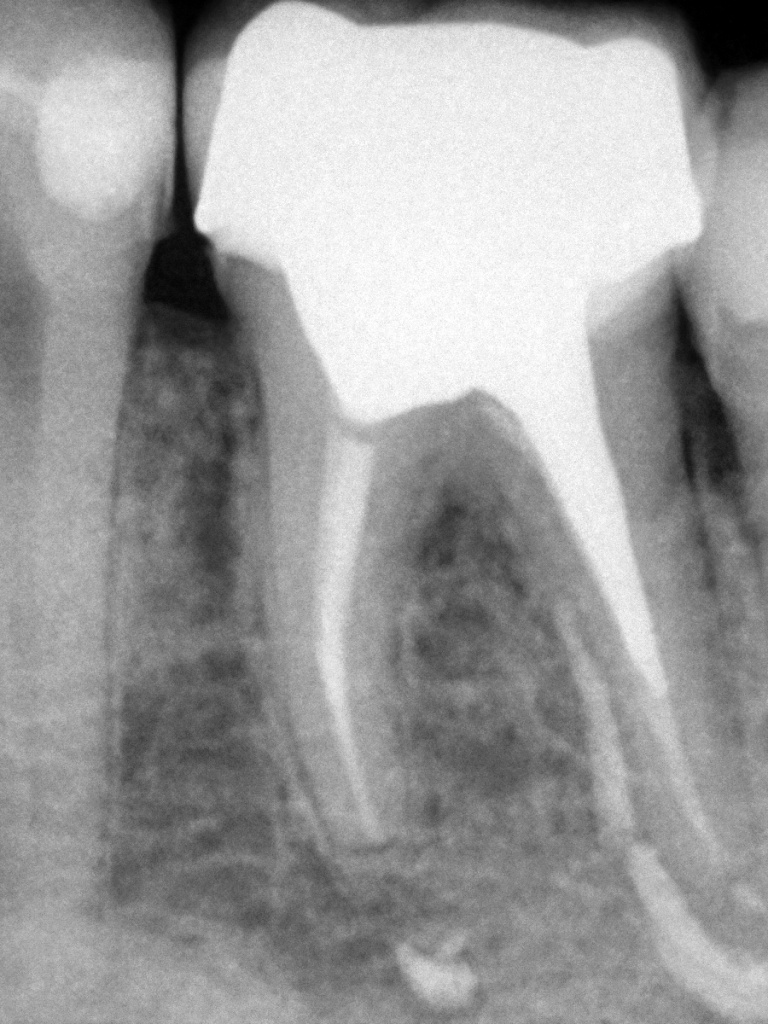

Снимки, сделанные с помощью нового визиографа Handy (см. рис. 3), говорят сами за себя. Рассмотрим слой за слоем, что скрывается под герметичным корпусом датчика и противоударным слоем, чтобы понять преимущества устройства.

Рис. 3. Снимки, сделанные с помощью визиографов HDR-500 и HDR-38